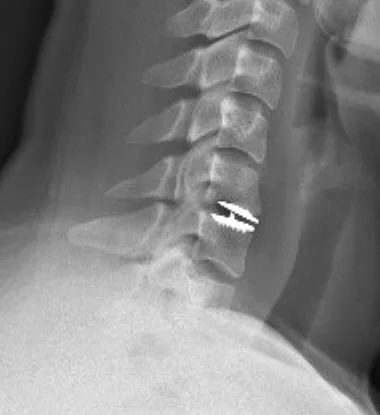

Postop X-ray after cervical arthroplasty

A postoperative X-ray showing an arthroplasty device in place.